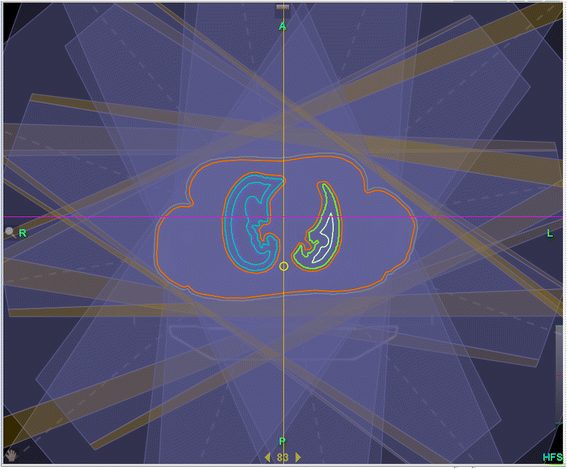

Background: The new TomoDirect™ modality offers a non-rotational option with discrete beam angles. We have investigated this mode for TBI with the intention to test the feasibility and to establish it as a clinical routine method. Special foci were directed onto treatment planning, dosimetric accuracy and practical aspects.

Patients and methods: TBI plans were calculated with TomoDirect™ for a Rando™ phantom and all patients with an intended fractionated total body irradiation between November 2013 and May 2014 (n = 8). Finally, four of these patients were irradiated with TomoDirect™. Additionally we studied variations in the modulation factor, pitch, field width of Y-jaws and dose grid during optimization. Dose measurements were performed using thermoluminescent rods in the Rando™ phantom, with the Delta4® and with ionization chambers in a solid water phantom.

Results: For all eight calculated plans with a prescribed dose of 12 Gy Dmean was 12.09-12.33 Gy (12,25 ± 0.08 Gy), D98 11.2-11.6 Gy (11.45 ± 0.12 Gy) and D2 12.6-13.1 Gy (12.94 ± 0.13 Gy). Dmean of inner lungs was 8.73 ± 0.22 Gy on the left side and 8.69 ± 0.27 Gy on the right side. When single planning parameters are varied with otherwise constant parameters, the modulation factor showed the greatest impact on dose homogeneity and treatment time. The impact of the pitch was marginally, and almost equal homogeneity can be obtained with field width of Y-jaws 5 cm and 2.5 cm. Measurements with thermoluminescent rods (n = 25) in the Rando™ phantom showed a mean dose deviation between measured and calculated dose of 0.66 ± 2.26%. 18 of 25 TLDs had a deviation below 3%, seven of 25 TLDs between 3% and 5%.

Conclusion: TBI with TomoDirect™ allows a superior homogeneity compared to conventional methods, where lung blocks are widely accepted. The treatment is performed only in supine position and is robust and comfortable for the patient. TomoDirect™ allows the implementation of organ-specific dose prescriptions. So the discussion about the balance between the need for aggressive treatment and limited toxicity can be renewed with the new potentials of TomoDirect™ - for children as well as for adults - and possibly yield a better clinical outcome in the future.